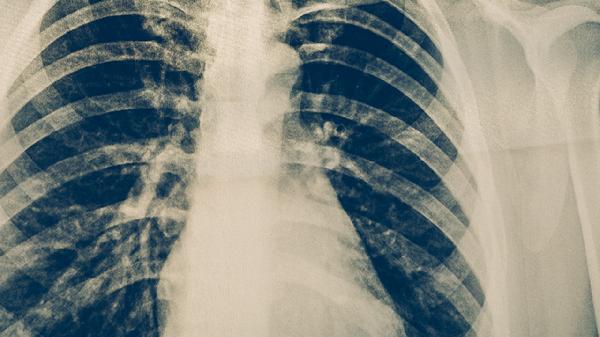

肺結(jié)核主要由結(jié)核分枝桿菌感染引起,常見誘因包括免疫力低下、密切接觸感染者、營(yíng)養(yǎng)不良等。肺結(jié)核的產(chǎn)生過程涉及細(xì)菌入侵、免疫反應(yīng)及肺部組織損傷三個(gè)階段。

結(jié)核分枝桿菌通過空氣飛沫傳播進(jìn)入呼吸道,在肺泡巨噬細(xì)胞內(nèi)繁殖。初期感染可能無癥狀,細(xì)菌可長(zhǎng)期潛伏。當(dāng)免疫力下降時(shí),潛伏菌重新活躍繁殖,導(dǎo)致活動(dòng)性肺結(jié)核。典型表現(xiàn)為咳嗽、低熱、夜間盜汗,需使用異煙肼片、利福平膠囊、吡嗪酰胺片等抗結(jié)核藥物聯(lián)合治療。

艾滋病、糖尿病等慢性病會(huì)削弱細(xì)胞免疫功能,使結(jié)核菌更易突破免疫防御。長(zhǎng)期使用免疫抑制劑的患者感染風(fēng)險(xiǎn)顯著增加。這類人群可能出現(xiàn)不典型癥狀如乏力、體重下降,需通過結(jié)核菌素試驗(yàn)和胸部CT輔助診斷,治療時(shí)需調(diào)整基礎(chǔ)疾病用藥方案。